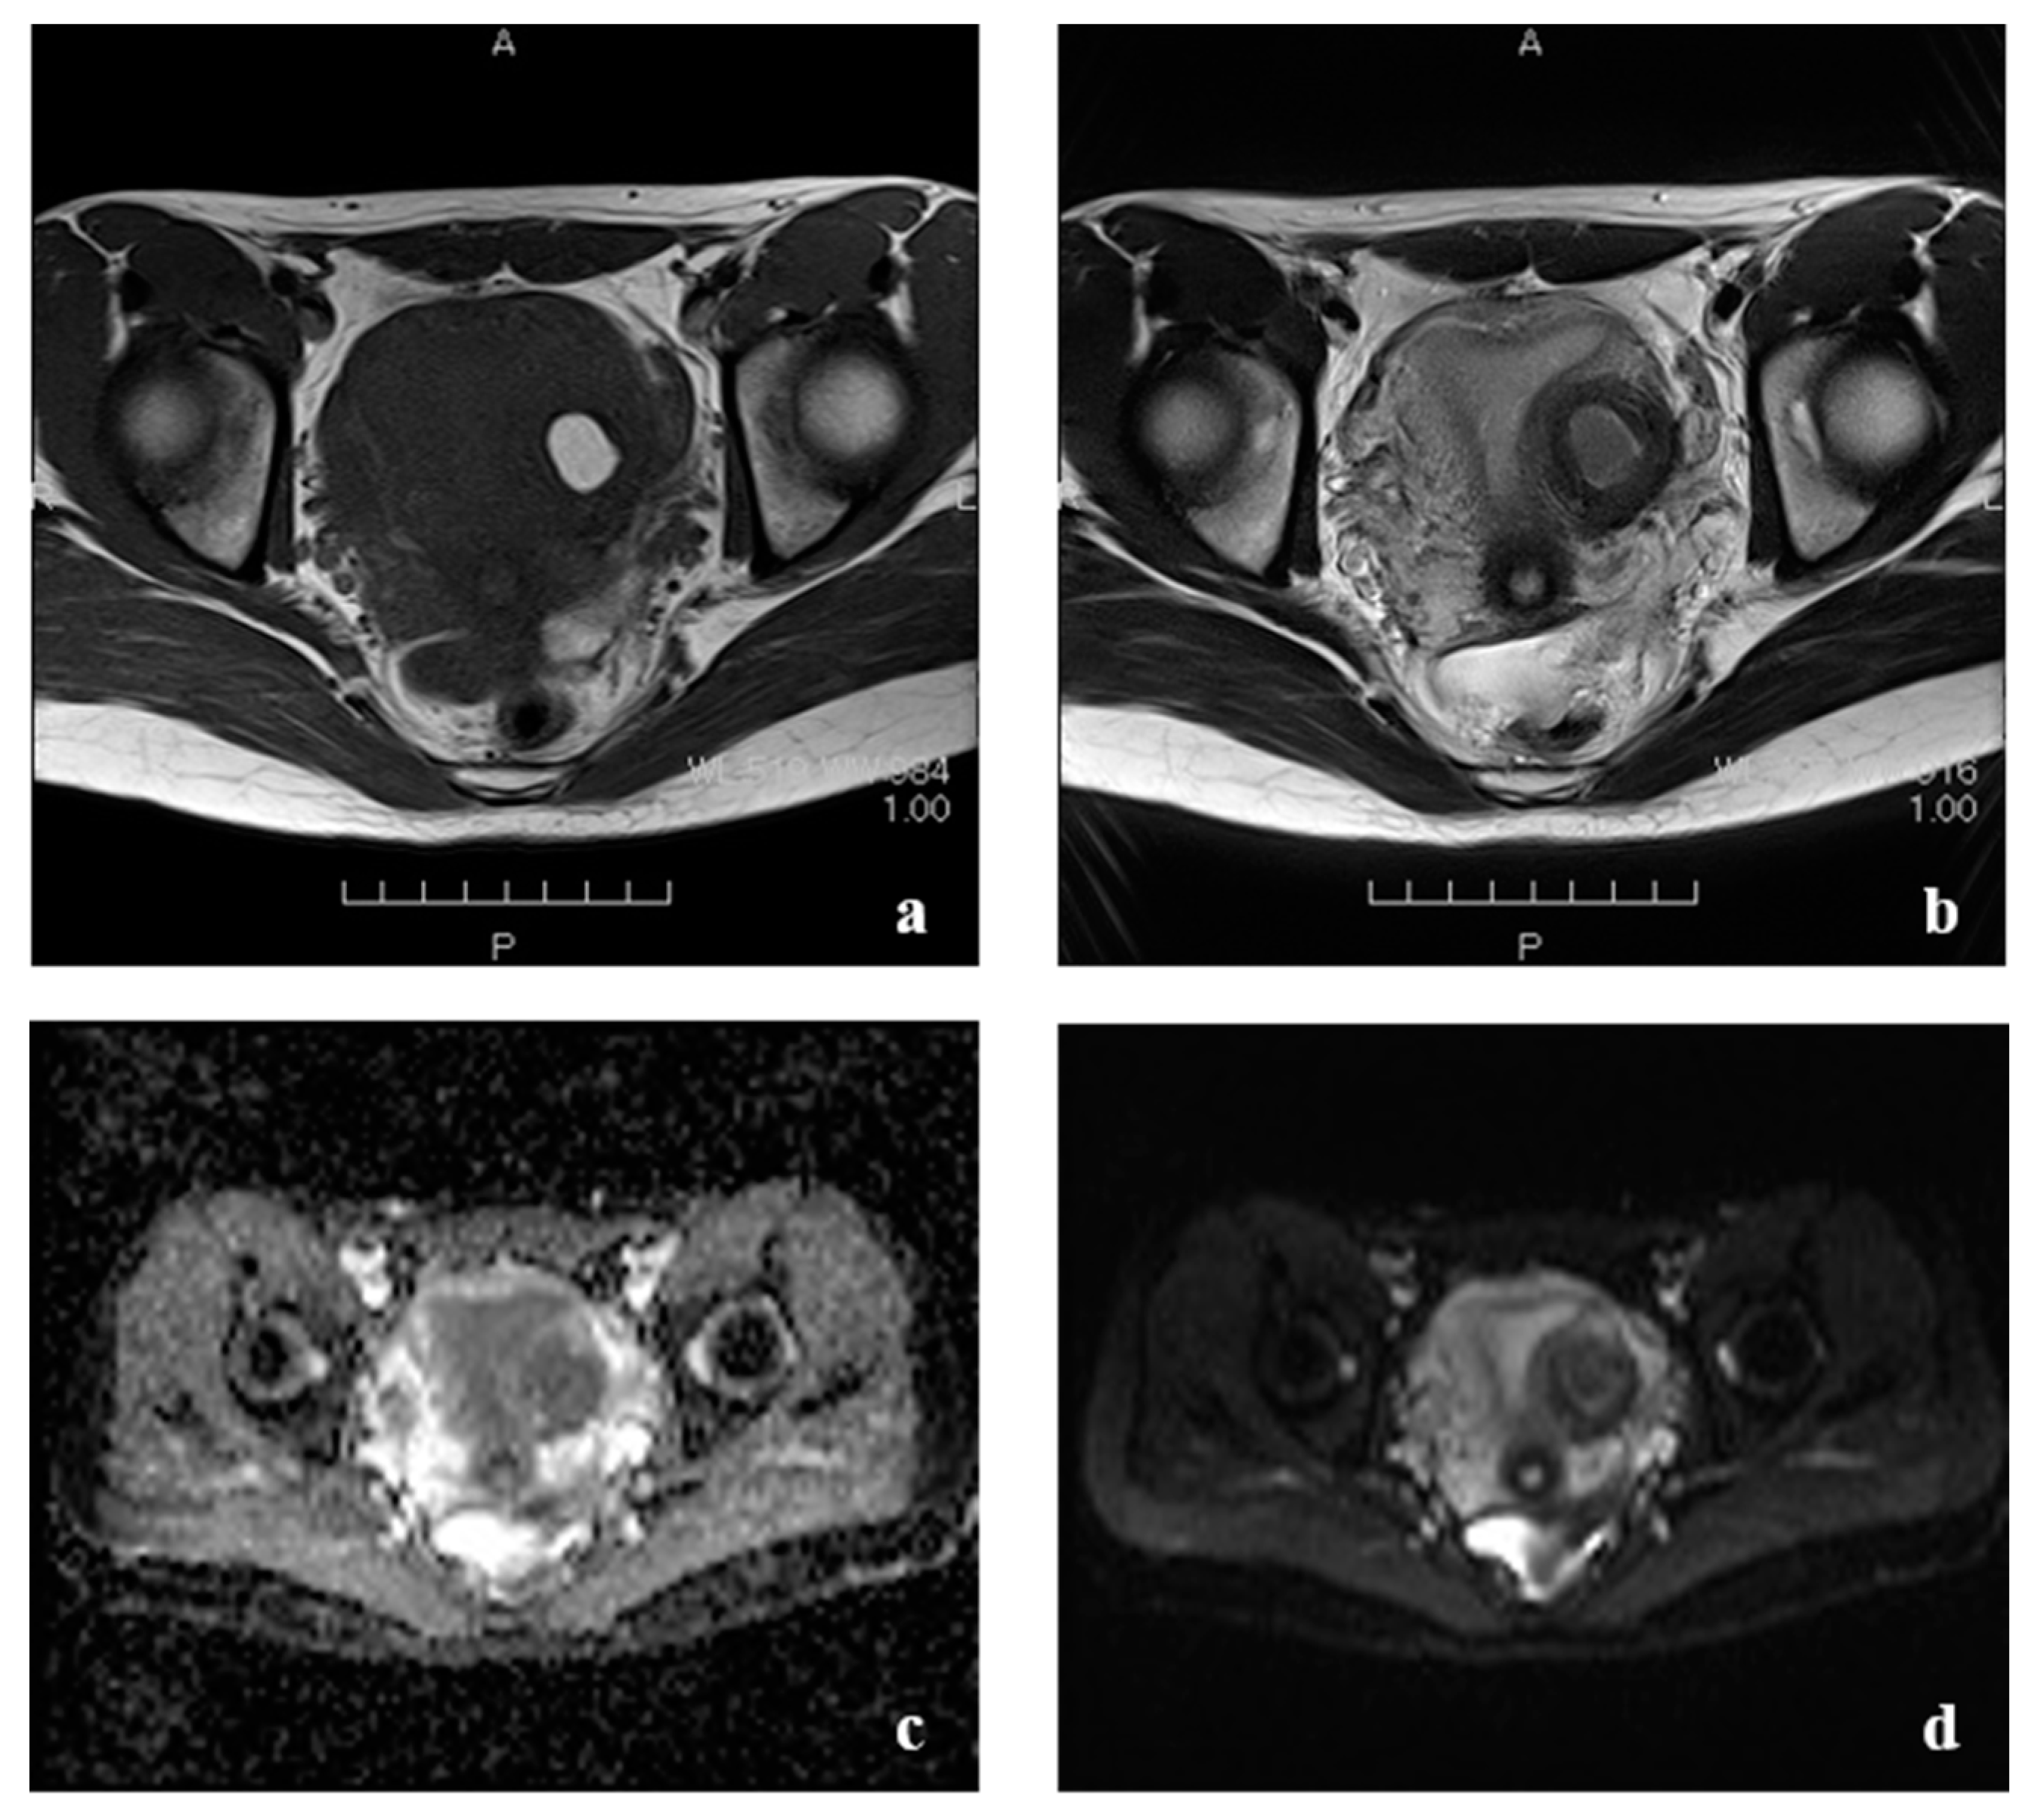

2. Case Presentation